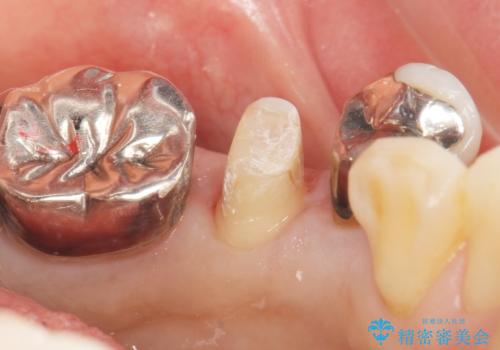

精査したところ、左下の小臼歯(左下5)の銀の詰め物の下に大きなう蝕を認めました。

患者様のご希望により、セラミッククラウンにより可及的にう蝕除去後の補綴及び歯並びの改善を行いました。

- ¥198,000 (土台×1本、仮歯・クラウン×2本) ※税込費用は治療当時の料金となります